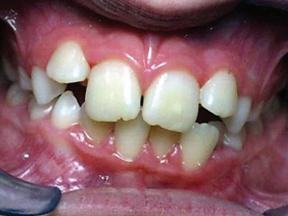

A tongue tie, or ankyloglossia, occurs when the thin tissue under the tongue (lingual frenulum) is too short or tight, restricting movement. While often associated with breastfeeding difficulties in infants—such as poor latch and nipple pain—it can also impact speech, dental development, and airway function throughout life. A holistic approach to tongue ties considers not just the mouth but the entire body, including airway health, posture, and overall wellness.

Tongue ties can contribute to a wide range of symptoms beyond feeding difficulties. In infants, they may cause reflux, excessive gas, prolonged feeding times, and poor weight gain. As children grow, unresolved tongue ties can lead to speech delays, difficulty pronouncing certain sounds, and even picky eating due to sensitivity to food textures.

In adulthood, tongue ties can contribute to jaw tension, TMJ disorders, poor sleep quality, snoring, mouth breathing, and even chronic headaches or neck pain. Since the tongue plays a crucial role in airway function, restricted movement can impact breathing patterns, leading to long-term health concerns.